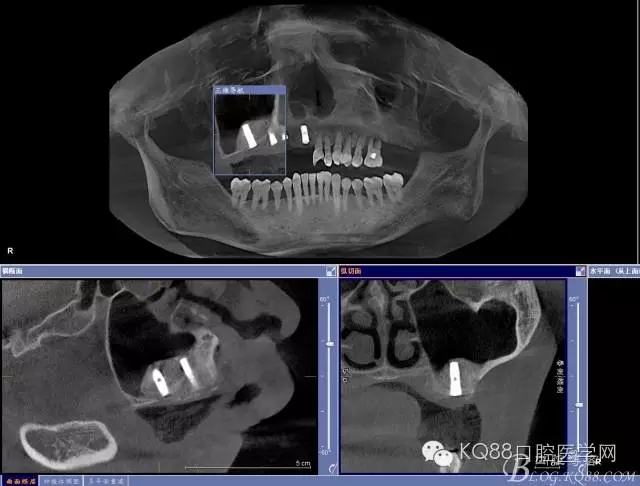

輔助檢查:ct示骨密度良好,11 12區(qū)域骨下有一水平向埋伏牙,15 16區(qū)域骨高度2.5-3mm,骨寬度6-9mm。

金剛砂球鉆制備橢圓形骨窗,遠(yuǎn)中邊緣延伸到上頜結(jié)節(jié),取下骨島,骨角和尖銳的邊緣打磨圓鈍,暴露上頜竇黏膜,分離提升上頜竇黏膜。

定位桿定位,擴(kuò)孔,備洞,bio-oss骨粉和CGF混合后充填竇腔

植入植體,骨島覆蓋上頜骨側(cè)壁骨窗

bio-guide屏障膜覆蓋側(cè)壁骨窗,牙槽嵴頂缺損部位植骨,嚴(yán)密縫合。